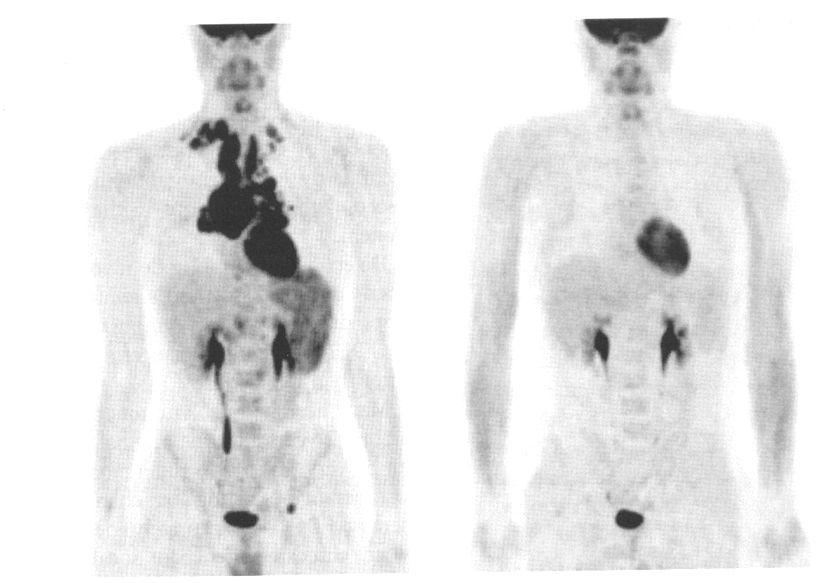

what does this image show

melanoma (diffuse) whole body

melanoma (scale area)

the image on the left is pre or post therapy for lymphoma

pre therapy

the image on the right is pre or post therapy for lymphoma

post therapy